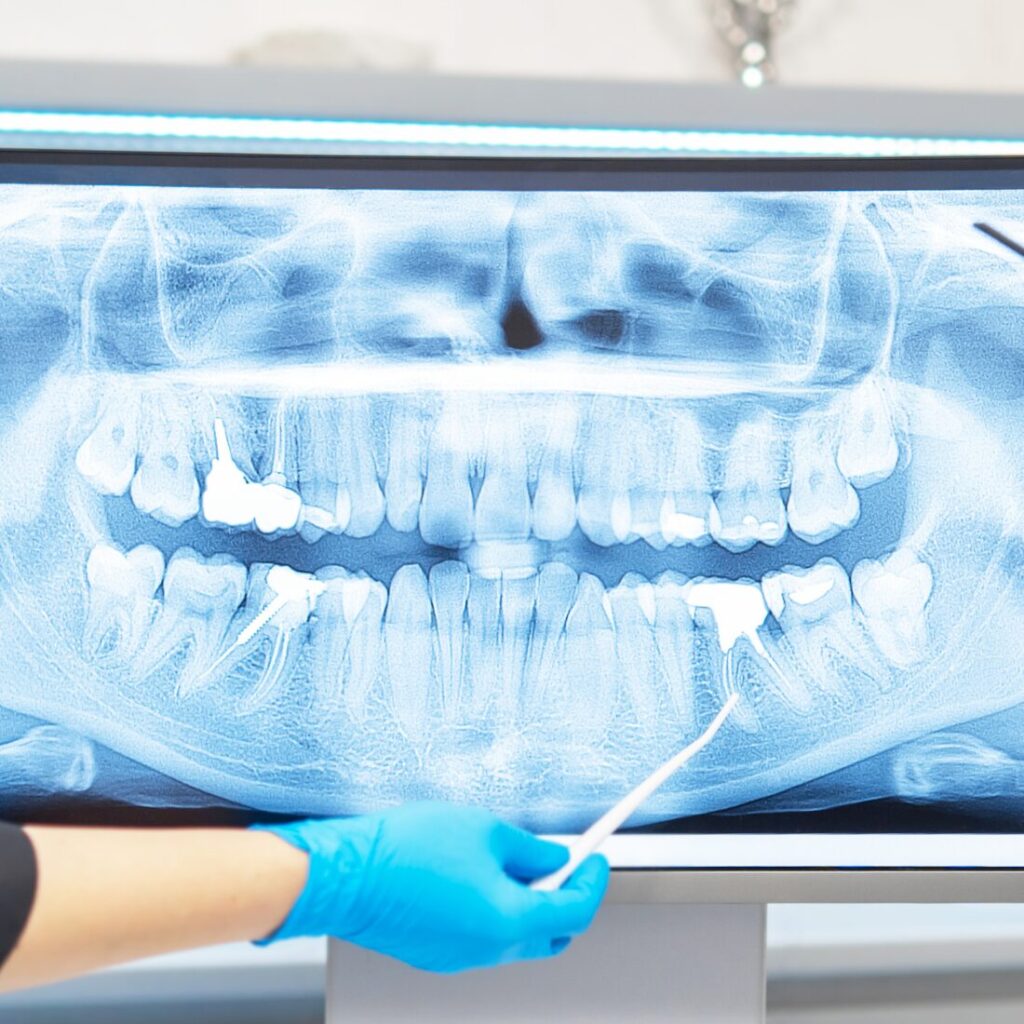

W ortodoncji dorosłych każdy milimetr ma znaczenie. Położenie korzeni, grubość kości, tor ruchu żuchwy, sytuacja w stawach skroniowo‑żuchwowych i przebieg nerwów – tego wszystkiego nie widać na zwykłym zdjęciu panoramicznym.

Tomografia stożkowa, czyli badanie 3D, pozwala zobaczyć struktury twarzoczaszki w trzech wymiarach i w przeciwieństwie do:

- pantomogramu (RTG panoramicznego) – który daje obraz 2D,

- zdjęć punktowych – pokazujących fragment,

umożliwia pełną analizę:

- położenia zębów i korzeni w kości,

- grubości i przebiegu kości wyrostka,

- zatok, stawów, dróg oddechowych,

- relacji między zębami, korzeniami i nerwami.

To nie jest „ładniejsze zdjęcie” – to dokładna mapa anatomiczna, bez której w wielu dorosłych przypadkach nie da się leczyć bezpiecznie i świadomie.